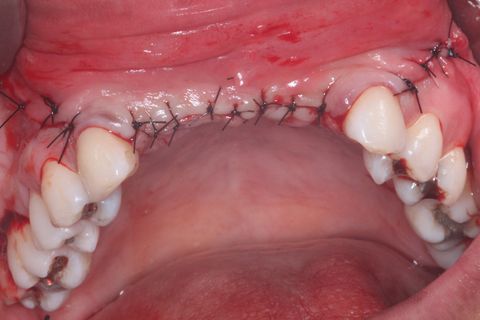

Sutura

Sutura final